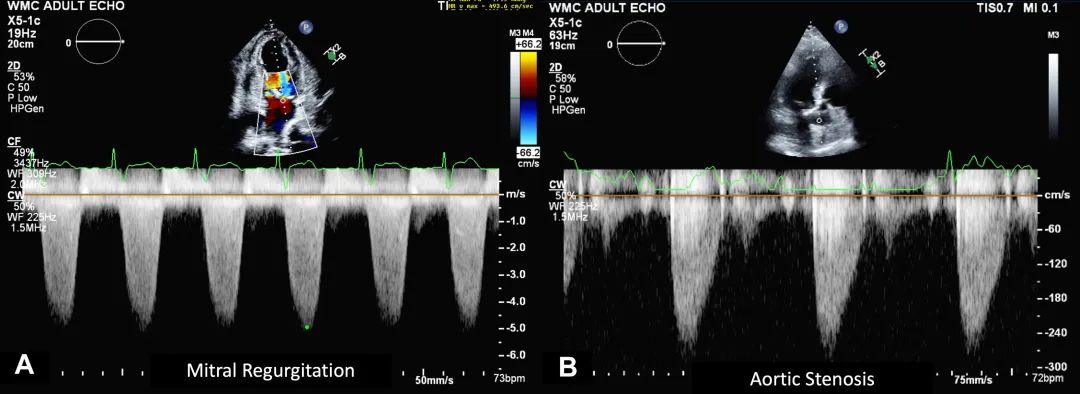

1、不要将二尖瓣反流流速误认为主动脉瓣狭窄流速。注意多普勒波形起始时间有助于区分这两种情况。二尖瓣反流多普勒波形呈圆形全收缩期波形,发生于等容收缩期和等容舒张期期间。而主动脉瓣狭窄的多普勒波形呈圆形但较尖锐,发生在等容收缩期之后但在等容舒张期之前的心脏收缩期内(图16)。扫描时,主动脉瓣位置偏前方(朝向胸壁前方),二尖瓣则更靠近中央位置(朝向胸骨)。

图16. 二尖瓣反流与主动脉瓣狭窄多普勒波形的比较

(A) 二尖瓣反流的多普勒波形呈圆滑轮廓,出现在心动周期的等容收缩期和等容舒张期。(B) 主动脉瓣狭窄的多普勒波形呈圆滑但稍尖锐的速度波形,出现在收缩期内,即等容收缩期之后但在等容舒张期之前。